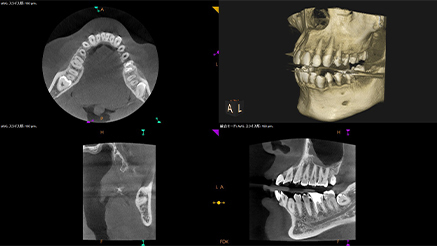

歯科用CTとシミュレーション

正確でリスクの少ない手術をめざし、歯科用CTによる検査とシミュレーションソフトによる検査を実施しています。

まずCT検査で、あごの骨の厚みや高さ、神経や血管の位置を把握。次に専用のソフトを使い、インプラントを埋め込む位置や方向などをシミュレーションします。

その後、シミュレーションデータをもとにサージカルガイド「BioNa」と呼ばれる装置を作製。事前に治療計画を立て、サージカルガイドを活用することで手術時間の短縮が可能です。

こうした工夫も、患者さまの身体的・精神的な負担を減らす上で大切です。